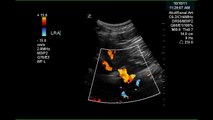

Color Doppler and pulsed Doppler demonstrate a stenotic portion of the renal artery. Parvus tardus is evident in Doppler wave=forms in the renal parechyma.\r